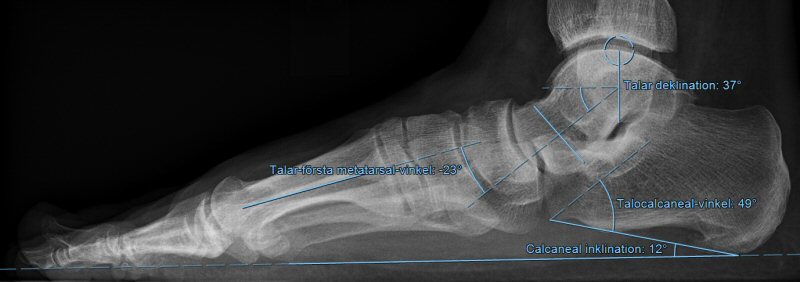

• Beställ belastad slätröntgen av fotled och fot [3]

• Innan ev. operation så bör belastad röntgen med frontal- och sidobild genomföras (framför allt för att avgöra eventuell artros, grad av dislokation i TN-led och nivådiagnostik på ledkollaps). [1]